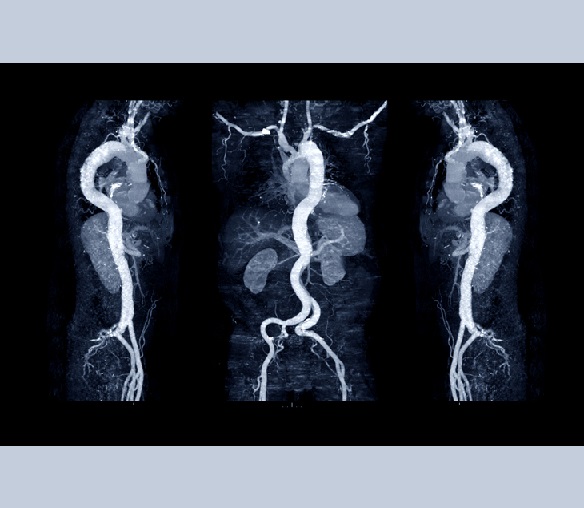

San Camillo Forlanini Hospital in Rome integrated an AI-powered 3D simulation system for planning endovascular treatments of cerebral aneurysms. Over 120 cases were treated in a year, with the AI system significantly reducing patient risk and unnecessary device use, improving safety and lowering costs.[AI generated]